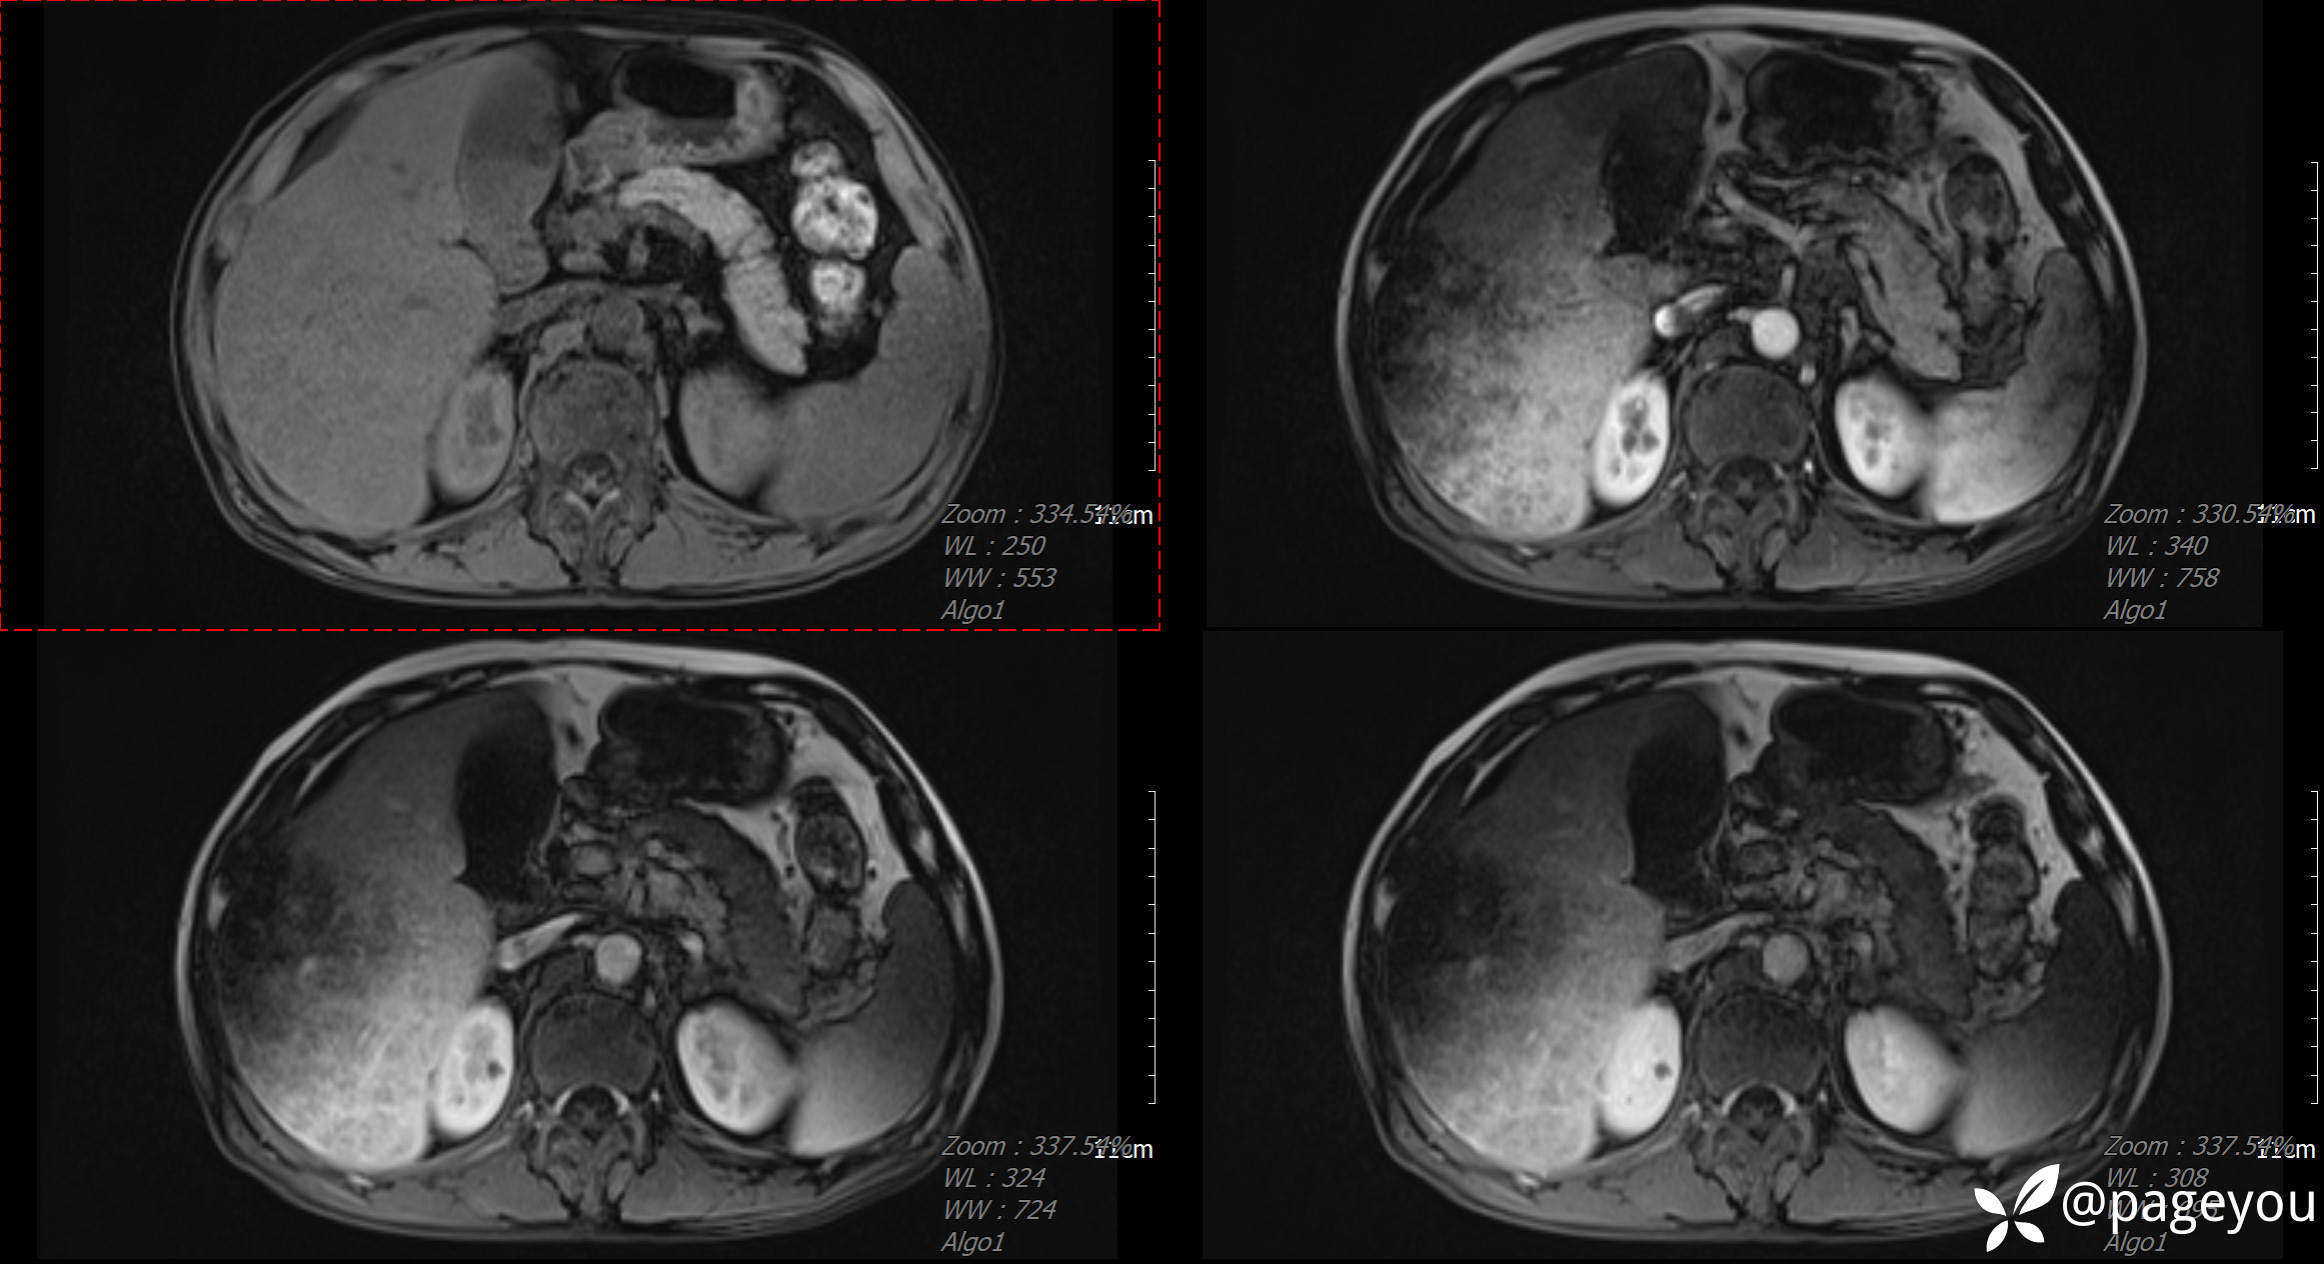

MRI检查: